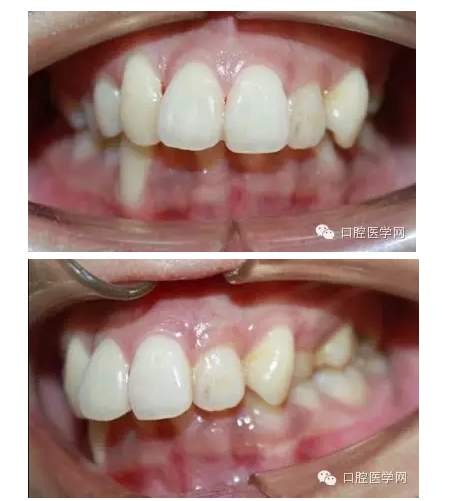

重度高角深覆合患者一例 科貿(mào)嘉友口腔收錄

這是一位我同事接診的一位患者,成年女性,安氏II類,高角,下頜后縮,重度深覆合,上下中線右偏,原本做過一次矯正,4個4已經(jīng)拔除。

這個患者,II類高角,下頜后縮,所以我們不能抬高磨牙,另外兩個上頜中切牙牙根短小,也不能大幅壓入。